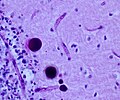

General microscopic

Features:[1]

• +/-Vacuolated muscle fibres.

• acid phosphatase+ve in vaculoes.

• PAS+ve.

• Cytoplasmic (lysosomal) vacuoles (Acid phosphatase +ve).

• Muscle fibers with vacuoles enlarged.

• Type 1 fibers more often affected.

• PAS+ve deposits.

• Autophagic (Lysosomal) vacuoles in electron microscopy.